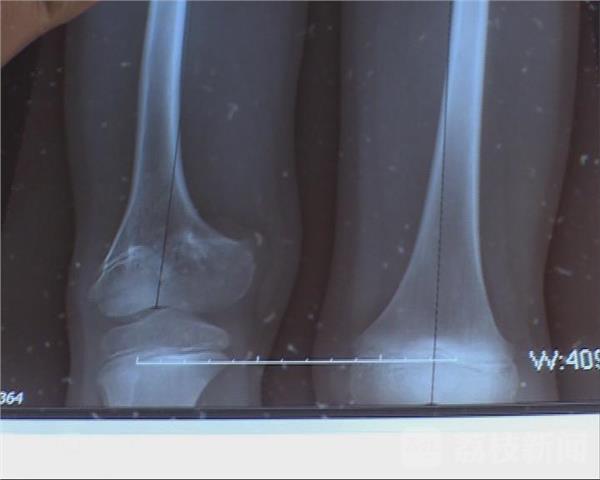

11月28日下午,九岁的童童来到淮安市妇幼保健院进行身体检查,两个月前他接受了淮安首例“断骨增高”手术,从检查的结果来看,他的右腿已经延长了近8厘米。

经过两个月的治疗,术前童童双腿长度差距是5.98厘米,术后右腿生长了7.78厘米。比左腿还长了1.8厘米。医生表示之所以要多出这1.8厘米,是因为由于先天原因,童童双腿生长速度不一致,右腿生长较慢,所以要预留一些生长的空间。